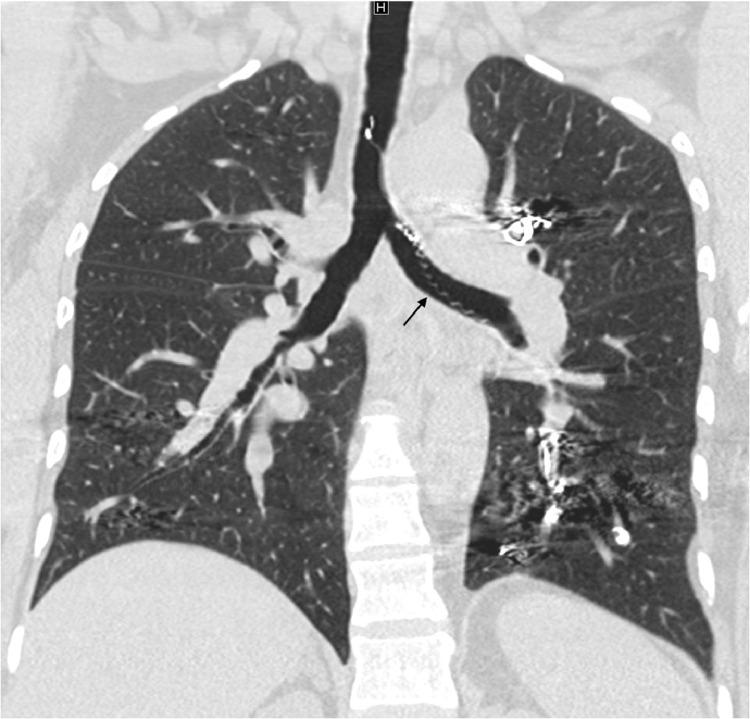

Pulmonary arteriovenous malformations develop in approximately 50% of hereditary hemorrhagic telangiectasia patients. Pulmonary arteriovenous malformations are often treated with coil embolization therapy. We report a case of a 45-year-old female with multiple pulmonary arteriovenous malformations due to underlying hereditary hemorrhagic telangiectasia who had undergone 14 coil embolization procedures over 16 years. She presented with sudden onset severe, unremitting, nonproductive cough from a foreign body sensation in the airway. Computed tomography of the chest demonstrated a metallic foreign body extending from the left lower lobe of the lung into the left mainstem bronchus and trachea. Bronchoscopy-guided removal of the foreign body revealed an intact embolization coil placed 8 years prior to presentation had partially migrated through the vessel and airway walls into the airway lumen, extending from the left lower lobe bronchus to the left mainstem bronchus. Coil migration is a rare, but potentially dangerous, complication of coil embolization therapy.

约50%的遗传性出血性毛细血管扩张症患者会出现肺动静脉畸形。肺动静脉畸形通常采用弹簧圈栓塞疗法进行治疗。我们报告一例45岁女性患者,因潜在的遗传性出血性毛细血管扩张症患有多发性肺动静脉畸形,在16年期间接受了14次弹簧圈栓塞手术。她因气道内有异物感而突然出现严重、持续、无痰咳嗽。胸部计算机断层扫描显示一个金属异物从左肺下叶延伸至左主支气管和气管。支气管镜引导下取出异物发现,一个在就诊前8年放置的完整栓塞弹簧圈已部分穿过血管壁和气道壁进入气道腔,从左肺下叶支气管延伸至左主支气管。弹簧圈移位是弹簧圈栓塞治疗一种罕见但可能危险的并发症。